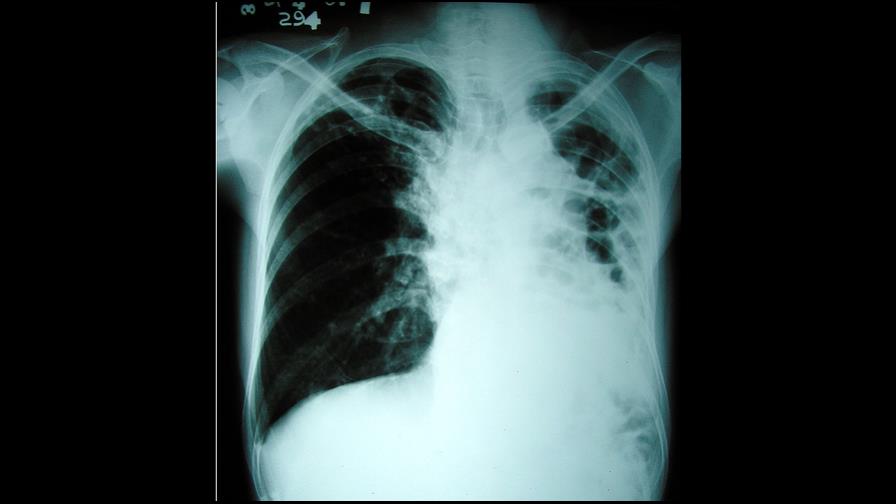

tuberculosis.